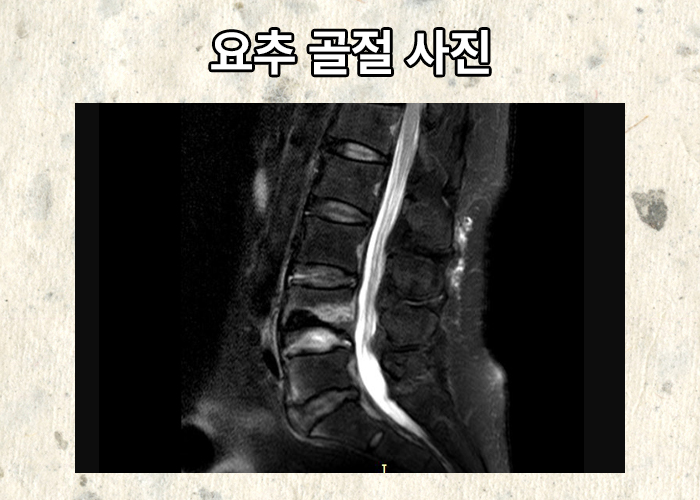

요추 4번 압박골절 진단받은 나@@님은 허리보조기 착용하며 보존적 치료 받게 되었습니다. 최소 3개월 간의 휴직이 필요했고 요양하시며 통증은 점점 가라앉았지만 충분한 보상이 필요하셨죠.

의뢰인은 요추4번 척추압박골절 비수술

산재 장해등급 12급 16호

인정받을 수 있었습니다. 산재 장해등급은 정해진 일수 * 평균임금 지급되는데요 1등급의 차이도 크기에 오차나 누락없는 산재 장해등급을 인정받는 것이 중요할 것입니다. 산재 장해등급 청구 아직 진행하지 않으셨다면 자신의 장해가 얼마나 해당되고 어떤 도움을 받을 수 있을지 상담 가능합니다.